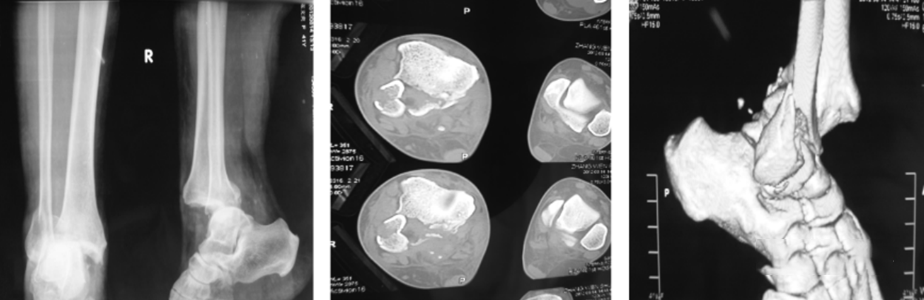

(1)Pilon 骨折

是指胫骨远端关节内骨折,常常由垂直暴力所致,常常合并腓骨骨折和严重的软组织损伤。